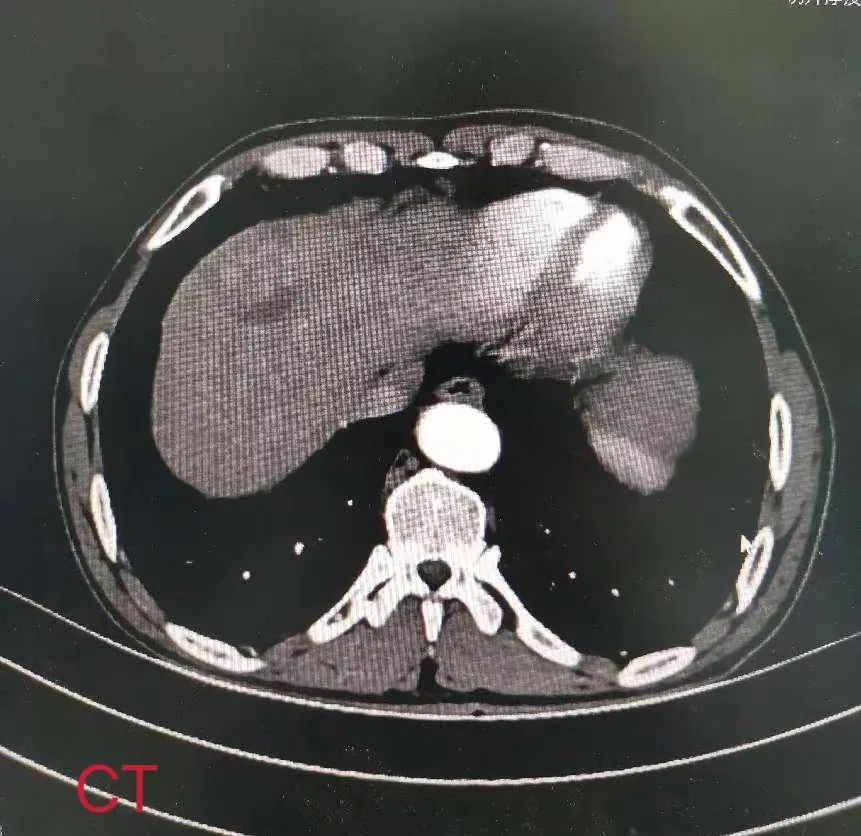

患者男性,66岁,因上腹疼痛3年,加重半月入院,既往大量饮酒史。入院后完善相关检查,腹部增强CT和MRI提示:肝脏占位性病变,约5*4*3cm大小,考虑肝癌。通过术前充分评估和讨论,明确肿瘤位于右前叶,紧靠肝中静脉。祁向军主任与患者家属充分沟通后,决定立即为患者施行手术治疗,考虑肿瘤在右前叶较局限,决定为其行腹腔镜下解剖性肝5、8段切除术。入腹后,按照预定手术方案,沿Laennec capsule进行解剖,在Glision鞘外解剖并离断肝5、8段的肝蒂,沿缺血线进行切除,完整切除肿瘤,探查腹腔无出血及胆漏后关腹。现患者已康复出院。